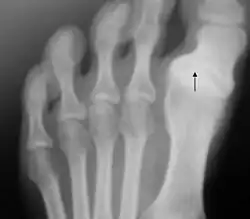

Un traumatismo frecuente en jugadores de rugby y otros deportes es el esguince de la articulación metatarsofalángica, también conocido como dedo del césped o del turf. Se suele producir por hiperdorsiflexión de la articulación. La clasificación de Jahss describe los diversos grados de luxación de esta articulación, y la clasificación de Clanton el grado de severidad del esguince.[23]​ En el fútbol son frecuentes los traumatismos en el dedo gordo del pie, que se producen cuando el pie del jugador está en posición pronada y con el talón al aire.[39]​ La enfermedad de Renander es una osteocondrosis que afecta a los sesamoideos, más frecuentemente en mujeres de entre 9 y 17 años, y que se produce por microtraumatismos deportivos.[87]